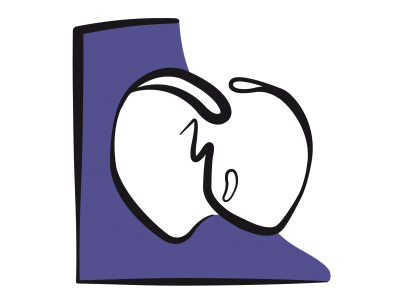

La boucle pression/volume (P/V) est une représentation graphique du travail ventriculaire au cours d'un cycle cardiaque. Elle a l'allure d'un quadrilatère posé sur la courbe de compliance et tournant en sens inverse des aiguilles d'une montre à partir du point télédiatolique (1); la contraction isovolumétrique conduit au point où commence l'éjection (2) et celle-ci se poursuit jusqu'au point télésystolique (3); la relaxation isovolumétrique amène au début du remplissage (4) et la boucle se termine au point télédiastolique (1) en suivant la courbe de compliance diastolique. Lorsqu'on varie le volume de remplissage d'un ventricule, tous ses points télésystoliques se trouvent alignés sur une quasi-droite appelée élastance maximale (Emax) dont la pente représente la contractilité du VG (Figure 23.6).

Figure 23.6: Boucle pression/volume lors d’insuffisance ventriculaire gauche (Ins VG , traits rouges) par rapport à une boucle normale (en jaune). La pente de la droite Emax (élastance maximale, qui reflète la contractilité, en bleu) et abaissée (en rouge) et la compliance ventriculaire (courbe verte) prend une allure restrictive (en rouge). Le volume éjecté (VS : volume systolique) diminue et le travail externe fourni (LVSW, left ventricular stroke work, représenté par la surface de la boucle) est plus faible. L’angle entre la pente Emax et la pente de la compliance est plus fermé. 1 : point télédiastolique; 1 →2 : contraction isovolumétrique; 2 : début de l’éjection; 2 → 3 : phase de l’éjection systolique; 3 : point télésystolique; 3 → 4 : relaxation isovolumétrique; 4 : début du remplissage; 4 → 1 : remplissage diastolique. VS: volume systolique (= Vtd – Vts). Le triangle compris entre la courbe de compliance, la droite Emax et la phase de relaxation isovolumétrique représente le travail de pression du VG.

La boucle P/V de l’insuffisance ventriculaire est caractérisée par un abaissement de l'élastance maximale (Emax), qui représente la force de contraction, et par une élévation de la courbe de compliance, qui représente la résistance au remplissage. Ces phénomènes conduisent à une diminution du volume systolique. Le rétrécissement de la surface de la boucle P/V traduit la baisse du travail éjectionnel fourni (stroke work). L’angle entre la pente Emax et la courbe de compliance étant étroit, une augmentation de la précharge par du remplissage déplace la boucle vers le haut et vers la droite, donc vers de plus grandes pressions et de plus grands volumes, mais n’améliore que faiblement le volume éjecté. Seul un effet inotrope positif augmente significativement le VS, parce qu’il redresse la pente de Emax (ouverture de l’angle entre la pente Emax et la courbe de compliance).